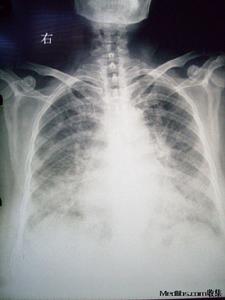

2.高山肺水腫(HAPE)是高山病中的惡性類型。一般在急性高原反應的基礎上發生,所以也有人認為高原肺水腫是急性高原病的合併症,也有可能在上呼吸道感染的基礎上惡化發生。其症狀類似與急性高山病但更為嚴重,在診斷上應予以區分,隨著病情的發展,病人出現嚴重的呼吸困難,咯泡沫痰,初為白色或淡黃色,後即變為粉紅色,量多者從口鼻湧出。患者煩躁不安,少數病人嗜睡。口唇、顏面青紫,體溫升高併合並感染,心率快。同時要注意高原肺水腫的“易感者”(患過高原肺水腫的人易再次發病)。在治療上病人應絕對臥床休息,同時給予大流量吸氧。口服速尿並注射地塞米松。同時將病人下撤至低海拔地區。值得注意的是,速尿會造成身體水分的急劇喪失,進而造成電解質紊亂,在飲食上注意保持鉀的攝入,同時病人的飲水量也應控制。